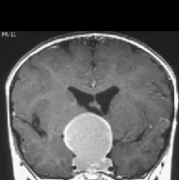

颅咽管瘤 是一种少见的中枢神经系统(CNS)良性肿瘤,被认为是由脑垂体附近的Rathkes囊残余形成。它们占全部原发性中枢神经系统肿瘤的不到1%,但却是儿童...

颅咽管瘤是一种来源于胚胎残余组织的良性肿瘤,颅咽管瘤约占儿童全部脑瘤的6%。任何年龄的人都有可能被诊断为颅咽管瘤,但在5到14岁之间较容易被诊...

颅咽管瘤 是起源于神经上皮的肿瘤,由鳞状细胞沿原颅咽管道长出。它们的发病率在每10万人年0.5至2.5之间,不因性别或种族而有所不同。颅咽管瘤占全部...

颅咽管瘤是什么病?颅咽管瘤占儿童脑肿瘤的 5% 到 15%,成人占 1%。虽然这些病变被认为是良性的,但它们具有浸润性和局部复发率高的特点。其来源于胚...